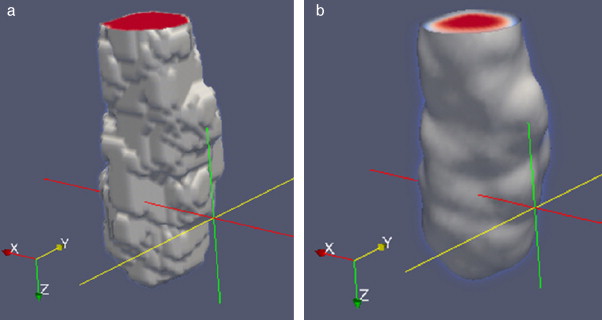

2.4.2. Suavizado de superficies

Las superficies rugosas o superpuestas presentes en las segmentaciones iniciales fueron corregidas con una rutina de suavizado combinando las técnicas de morfología matemática: dilatación y erosión con el filtro de Gauss . En Gonzalez y Woods [24] , se explica con mayor detalle estas técnicas. En la figura 13 se presenta un ejemplo de la aplicación de estas rutinas de remuestreo. En la figura 13 .a se muestra el volumen original segmentado con el método Level Set , en el cual se observa con superficies rugosas. En la figura 13 .b se observa el remuestreo aplicado al volumen de la figura 13 .a, lo cual generó un volumen más liso.

Figura 13. Remuestreo del volumen de la aorta obtenido con Level Set. (a) Volumen original de la aorta descendente. (b) Remuestreo del volumen (a). |

3.1.3. Remuestreo y exportación a CAD

En el siguiente paso, se realizó el remuestreo del modelo geométrico segmentado empleando dilatación morfológica con un elemento estructural en forma de esfera de radio 3 × 3 × 3 . Esta tarea fue necesaria para suavizar superficies superpuestas y rellenar posibles agujeros generados durante la segmentación. Este modelo fue guardado en formatos legibles por software de visualización y herramientas CAD como GiD, ParaView, Autodesk Inventor y Abaqus.

En la figura 16 se presenta el volumen final del ventrículo izquierdo con el inicio de la válvula aórtica (fig. 16 .a), el modelo final suavizado visualizado en ParaView (fig. 16 .b), el modelo en sólido visualizado en Autodesk Inventor (fig. 16 .c), el modelo en malla visualizado en GiD (fig. 16 .d) y el modelo discreto con los elementos finitos realizado con Abaqus (fig. 16 .e). Estos modelos han sido obtenidos a partir de IRM cardiovascular de un paciente con cardiopatía isquémica. Obsérvese que la protuberancia presente en la zona superior derecha del ventrículo izquierdo constituye una zona de necrosis conocida como cicatriz isquémica, la cual es alojada en el músculo del miocardio.

3.2.3. Remuestreo y exportación a CAD

Para mejorar el modelo geométrico inicial obtenido de la segmentación, se realizó el remuestreo a través de la técnica dilatación morfológica con un elemento estructural en forma de esfera de radio 3 × 3 × 3 , lo cual fue realizado con el fin de suavizar superficies superpuestas y rellenar posibles agujeros generados al utilizar la técnica de umbralización. El modelo geométrico fue guardado en formatos legibles por software de visualización y herramientas CAD como GiD, Paraview, Autodesk Inventor y Abaqus.